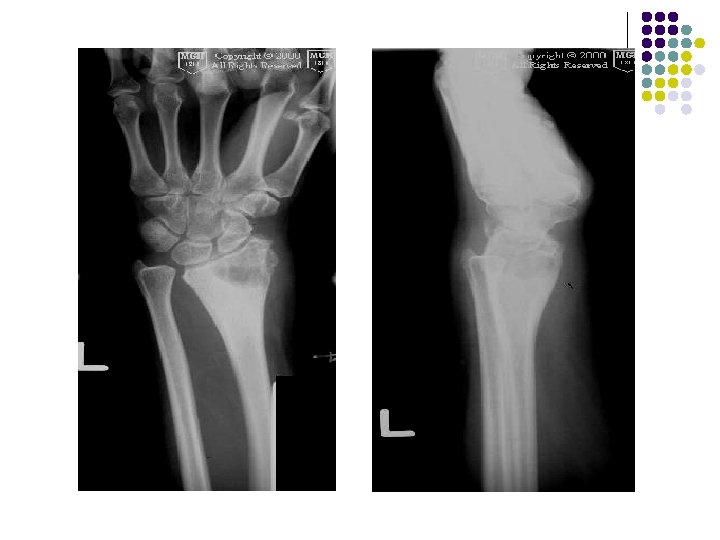

AP radiograph of the left wrist shows an expanded solitary lytic lesion involving closed epiphyses subarticular position of the distal ulna without rim of sclerosis or periosteal reaction which is typical for a giant cell tumor

Giant cell tumor of distal radius is eccentric and extend to the end of the bone